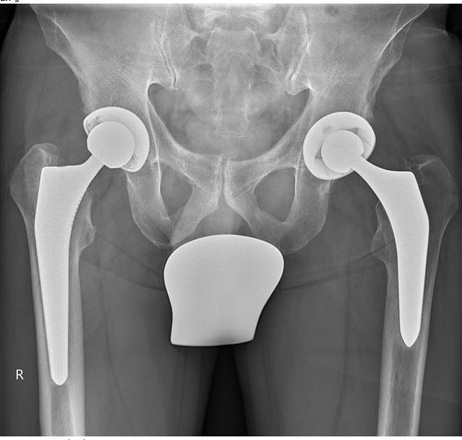

1.7

Trotz dem wurde das andere Hüftgelenk auch noch ausgewechselt.

Trotz Operationen sind die Schmerzen geblieben.

Beachtet man das Becken und die Gelenk-Stellungen sieht man nun auf der rechten Seite eine Verdrehung des Beckenlochs.

Der Beckenspalt ist immer noch hochgezogen. Durch die Verdrehung quetscht nun die linke Seite.

Man hat die Belastung verschoben.

Bei der Statik Kontrolle wurde der Beckentiefstand und der damit verbundenen seitlichen Oberkörper- Ausweichhaltung nicht beachtet.